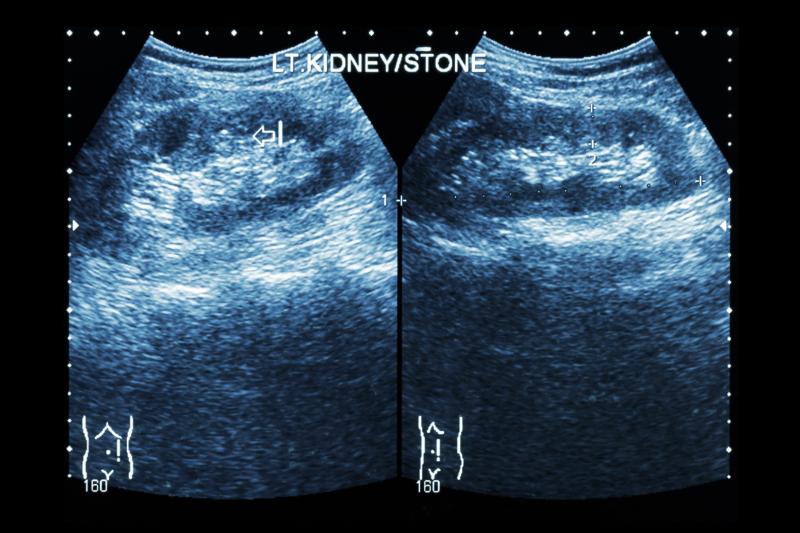

Of the six studies identified, three were RCTs and four had available data on renal stones. A total of 669 patients (mean age range, 4.4‒12.4 years) were analysed. The stone-free rate ranged between 21 percent and 90 percent in the SWL group and between 37 percent and 97 percent in the FU group.

In the meta-analysis of RCTs (n=302), FU exhibited significantly higher stone-free rate (relative risk [RR], 1.17, 95 percent confidence interval [CI], 1.04‒1.33; p=0.01), operative time (mean difference [MD], 16.4 minutes, 95 percent CI, 7.3‒25.5; p<0.01), and hospital stay (MD, 0.25 days, 95 percent CI, 0.14‒0.36; p<0.001) than SWL.